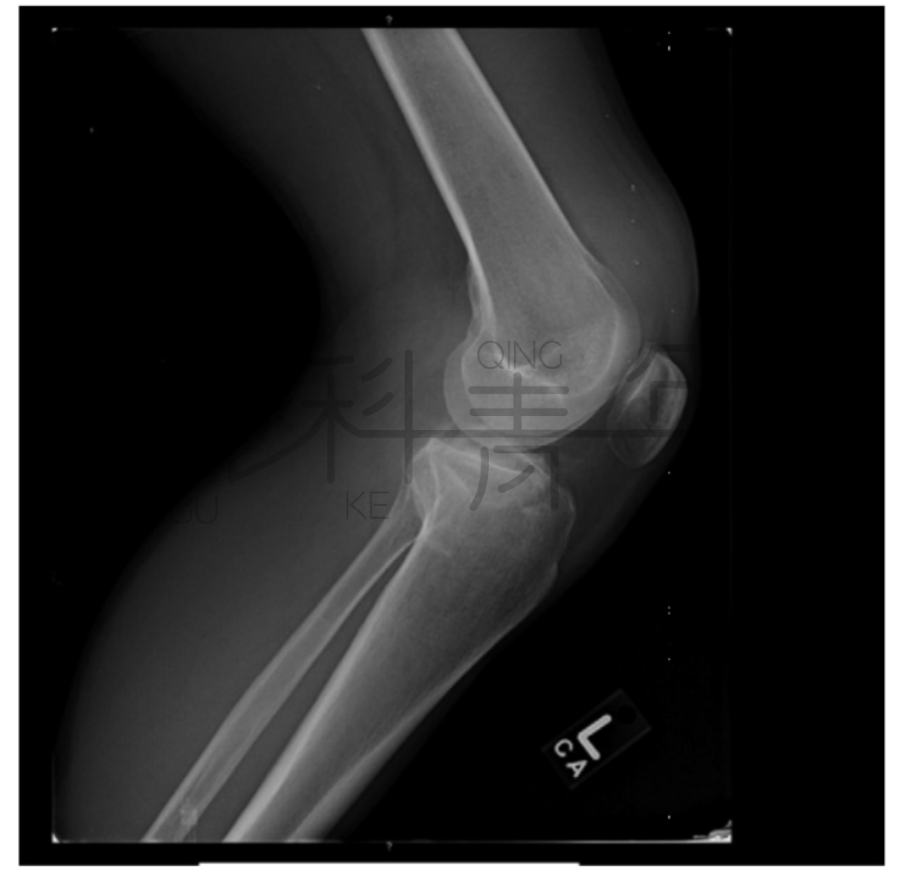

病例1在膝关节X线正位片上可见骨折间隙(a),侧位上可见明显关节积脂血症。

病例3一例膝关节外伤患者,在膝关节侧位X线上,积脂血症并不明显。